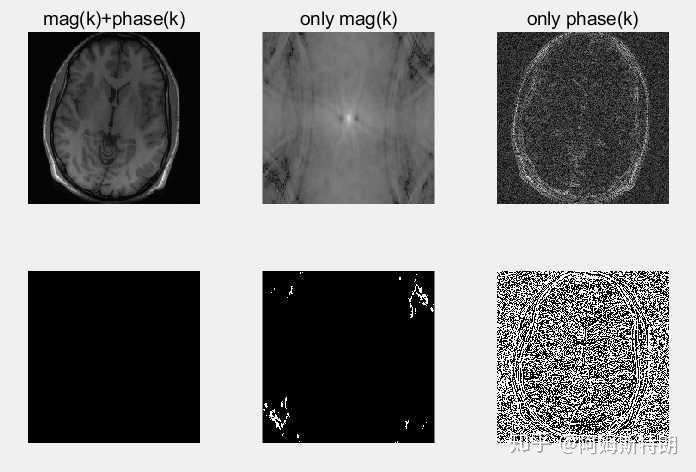

- 如果使得k空间的phase全部等于0,那么相当于平面波在相加的时候,都没有移动,所以图像一定会呈现一种周期性,而且中间的点一点很亮。这是因为复平面波没有移动,那么所有的平面波在中心点相位为0,exp(0)=1,因此相当于所有的幅度叠加在一起了。如下图:

- 如果使得k空间的magnitude全部等于1,那么相当于平面波在相加的时候,只有移动,而没有了各个波的大小信息,低频成分和高频成分全都一样了,所以图像应该比较嘈杂,变化比较剧烈,但是能看见大体的轮廓,如下图:

将上面三种情况放在一起比较,可见保留phase的k空间经过变换后得到的图像更接近于原来图像,只不过噪声较大。而保留magnitude的k空间变换后是一种周期的图像,变换缓慢。

可见,k空间中的phase保留的是位置信息,如果没有幅度或者,幅度错误,只是对比度会不同;而mag保留的是强度信息,没有phase的话,强度相加也是按照周期性相加。

因此:k空间中的幅度决定强度信息,相位决定位置位置信息。